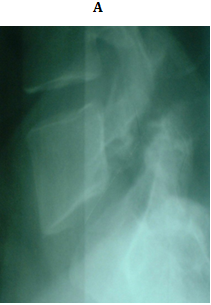

No implant failure was detected in the follow up radiographs. At the final follow up, radiological healing could be achieved bilaterally in all patients (86.6%) but four. Three of them had initial defects >3mm and one from 2-3mm, all at L5. For the healed cases, the mean time to union was 4.7 months. In the cases which did not heal, only 1 complained of significant back pain at final follow up. The other 3 did not complain of pain at final follow up (Figures 3 & 4).

Figure 4 A 23 years old female with double level spodylolyis at L4 and L5. (A, B) Preoperative plain radiographs. (C,D) 3 months after direct pars repair with cable screw construct at both levels.